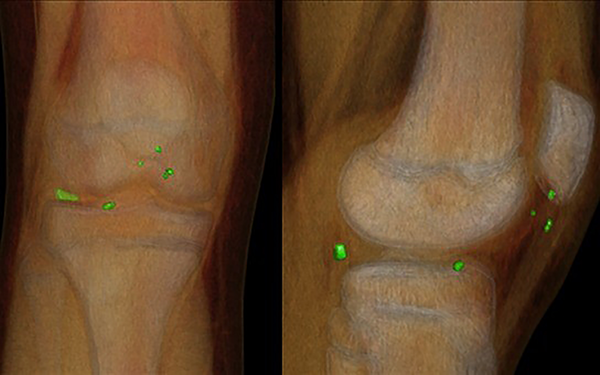

Previo a realizar la tomografía, la paciente reconsultó por aumento del dolor y el derrame articular. Esta vez presentaba déficit a la extensión y maniobra de McMurray positiva. Se realizó el estudio de imagen en el que se visualizaron dos cuerpos intraarticulares compatibles con vidrio, tanto en la región anterior como posterior del compartimento lateral (figs. 3 y 4).

Figura 4. Intensificación de fragmentos en TAC con reconstrucción 3D.